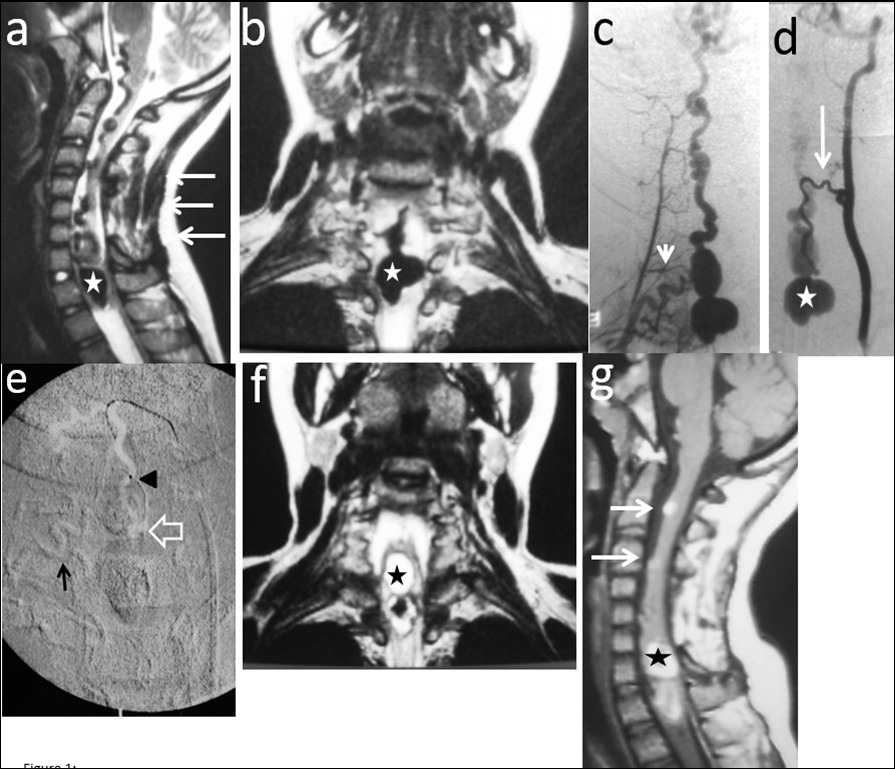

Figure 1.Case # 1: a) T2W sagittal and b) coronal MRI images showing a large bilobed varix in the anterior aspect of the spinal cord at the vertebral levels of C7 and T1 (star). Notice the large venous drainage ascending ventrally from the cervical spinal cord towards the brainstem (thin arrow). A previously C3 to C7 “decompressive” laminectomy was performed (arrows). c) Right thyrocervical trunk demonstrates that the main feeder to the fistula is the right artery of the cervical cord enlargement (short arrow). d) Another feeder from the ASA, branch of the left vertebral artery is visualized (thin arrow). The venous varix is shown (star). e) Roadmap image at the time of micro catheterization of the left ASA. The tip of the microcatheter (arrowhead) was further advanced to the fistulous site (open arrow) and 0.8 cc of 90% n-bca in lipiodol was injected. Also notice the glue cast injected in the artery of the cervical enlargement (thin arrow). f) MRI T2W FLAIR coronal and g) sagittal (postoperative day 5) showing fresh clot in the venous varix (star) with retrograde thrombosis of the ascending draining veins (arrows). The MR signal of the spinal cord remained normal.

Two out of 4 patients were diagnosed and studied preoperatively with both spinal MRI and CT scans, 1 patient with MRI and the other patient with CT/CT Angiography with 3D reconstruction. Large and tortuous flow voids with large to giant venous pouches or pseudoaneurysms (3 of our cases - type c) causing compression of the spinal cord were found lying ventrally and, in another one, posterolaterally to the spinal cord. Hyperintensity in T2W sequences in the spinal cord was noted in all of them. There were no cases where a hemorrhage was exhibited. The angiographic studies confirmed the 4 large or giant pouches at the draining vein fed by ASA and or PSA and ascending (2 cases), descending (1 case) or metameric (1 case) venous drainage. The blood flow was moderate in 1 case and very fast in the other 3 patients (see Table 2 and Figure 1, Figure 2, Figure 3, Figure 4).

We used transarterial approach and a single session achieving complete obliteration of the fistulae while preserving the normal vasculature, mainly the ASA, in all of our 4 cases using either different concentrations of n-bca alone tailored to the blood flow velocity (cases 1,2 and 3), or a combination of coils and onyx 18 (case 4). In this last case, the high flow fistula and the presence of a giant pseudoaneurysm at the venous varix compressing the spinal cord prompted us to deploy coils in the sac and in the draining vein to slow down the blood flow and decrease the chance of distal embolism. To date, we do not have Onyx of higher concentration than Onyx18 available in our country. In high flow macrofistulae, our strategy to slow down the flow to allow casting of the polymerizing embolic mixture in the fistulous site avoiding distal embolism includes lowering mean arterial pressure down to 60-70 mm Hg pharmacologically, by embolizing with concentrations of 66% of n-bca in lipiodol, as well as the placement of detachable coils in the event of very high flow with pseudoaneurysms at or very close to the fistulous site as a first step, to trap the liquid embolic material injected as second step (see Figure 1, Figure 2, Figure 3, Figure 4).